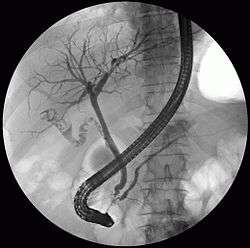

The diagnosis of choledocholithiasis is suggested when the liver function blood test shows an elevation in bilirubin and serum transaminases. Other indicators include raised indicators of ampulla of vater (pancreatic duct obstruction) such as lipases and amylases. In prolonged cases the INR may change due to a decrease in vitamin K absorption. (It is the decreased bile flow which reduces fat breakdown and therefore absorption of fat soluble vitamins). The diagnosis is confirmed with either an MRCP (magnetic resonance cholangiopancreatography), an ERCP, or an intraoperative cholangiogram. If the patient must have the gallbladder removed for gallstones, the surgeon may choose to proceed with the surgery, and obtain a cholangiogram during the surgery. If the cholangiogram shows a stone in the bile duct, the surgeon may attempt to treat the problem by flushing the stone into the intestine or retrieve the stone back through the cystic duct.

On a different pathway, the physician may choose to proceed with ERCP before surgery. The benefit of ERCP is that it can be utilized not just to diagnose, but also to treat the problem. During ERCP the endoscopist may surgically widen the opening into the bile duct and remove the stone through that opening. ERCP, however, is an invasive procedure and has its own potential complications. Thus, if the suspicion is low, the physician may choose to confirm the diagnosis with MRCP, a non-invasive imaging technique, before proceeding with ERCP or surgery.